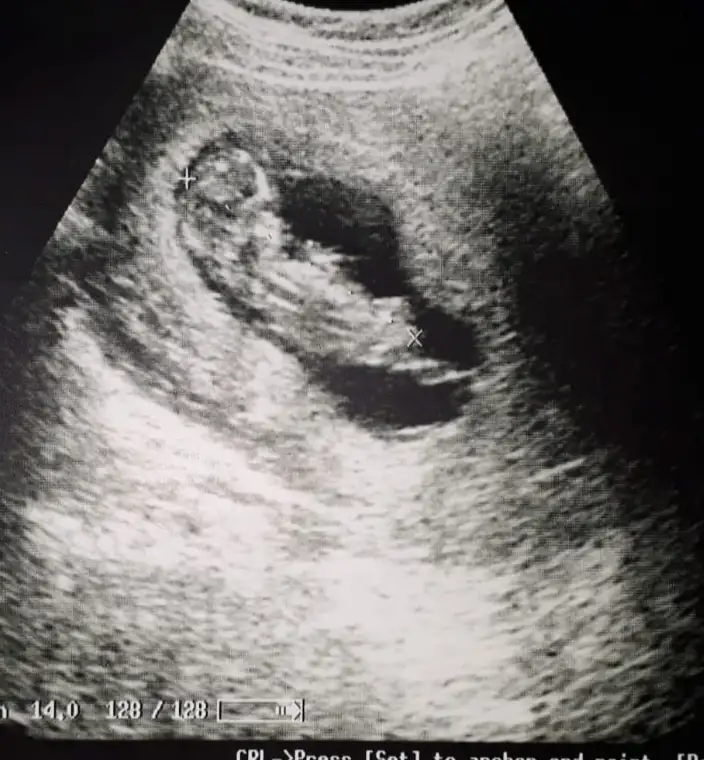

Nubtan hiç anlamıyorum cnm biriler yorumlarsa benzetmeye çalışacağımEki Görüntüle 2248081 kizlar cinsiyet tahmini yaparmisiniz

Hayirli olsun canimEki Görüntüle 2248081 kizlar cinsiyet tahmini yaparmisiniz

Canım kıza benziyorEki Görüntüle 2248081 kizlar cinsiyet tahmini yaparmisiniz

Günaydın cnm ben bunlardan pek anlamıyorum ama görüntü net olduğu için kıza benzettim . Senin mi bu? Gönlünden geçen olsun inşallahgünaydın kızlar bana da tahminde buluna bilir misiniz ☺☺